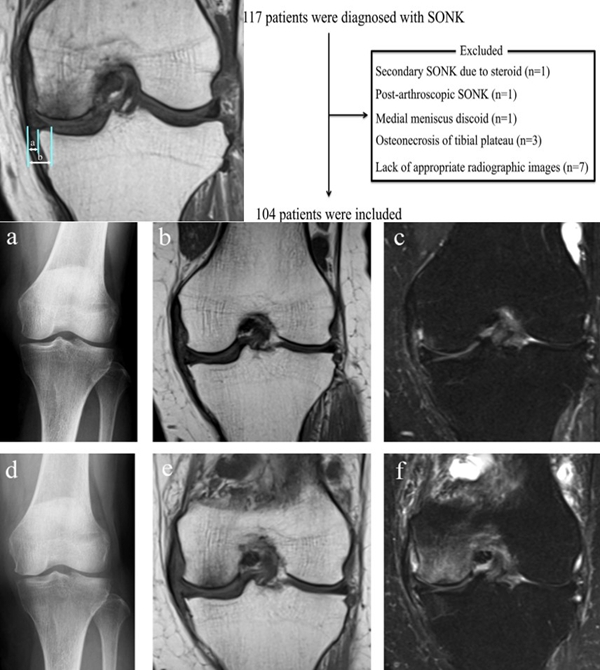

膝关节自发性骨坏死(spontaneous osteonecrosis of the knee,SONK)是指发生于股骨内侧髁负重面深层、原因不明的局部骨坏死,也可发生于股骨外侧髁或胫骨平台,在1968年由Ahlback等首先描述。

目前SONK诊断最常用的分期方法是1979年Koshino提出的分期法。Koshino分期基于临床和影像学的结果,将SONK分为四个阶段:

Ⅰ期:患者有膝关节症状,但影像学正常;

Ⅱ期:X线显示负重区变平,软骨下信号升高,周围有骨硬化;

Ⅲ期:受影响区域扩大和软骨下塌陷;

Ⅳ期:病变周围骨硬化和髁突周围骨赘形成的退行性阶段。

1979年Koshino分期

SONK与内侧半月板突出的相关研究中,100%(104)SONK中都有半月板突出,4个SONK在发病前因膝关节疼痛体检发现半月板突出,几个月后通过MRI检查显示存在 SONK。

研究证明半月板挤压是SONK的发病机制之一,半月板挤压的进展可能与SONK的发展有关。

a.患者,59岁女性,AP侧位片显示SONKⅠ期,FTA<180°;b.MRI T2显示病变深度<20mm,患者出现症状1年后保守治疗;c.75岁女性,X线显示SONKⅠ期,FTA>180°;d. MRI T2显示病变深度>20mm,患者于症状出现后11周行手术治疗